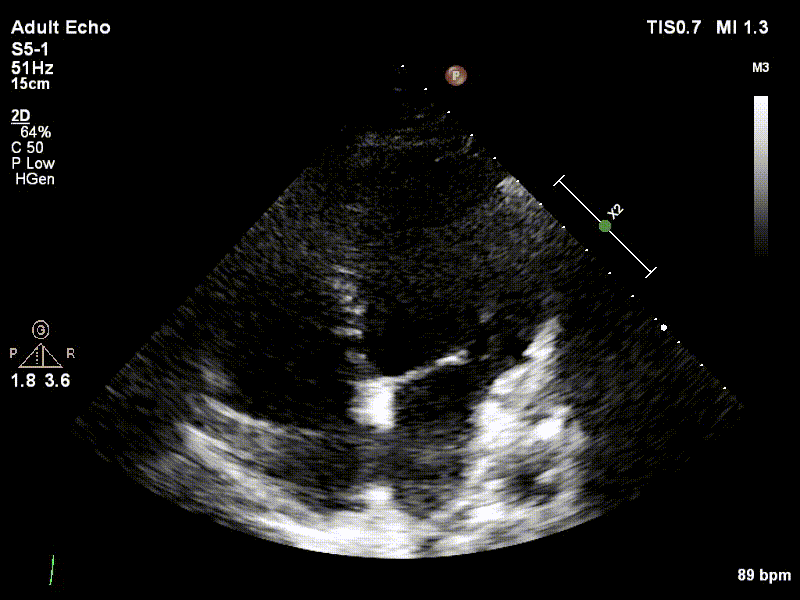

Example echocardiographic video used for model training and evaluation.